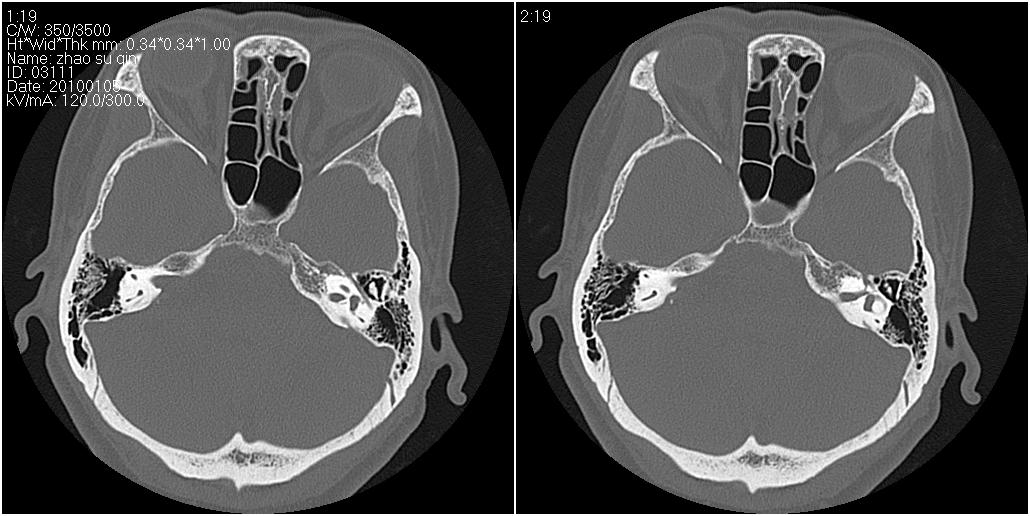

标题: CT24015:一个头部外伤患者进行鉴定,除了左侧筛板骨折,哪 [打印本页]

标题: CT24015:一个头部外伤患者进行鉴定,除了左侧筛板骨折,哪

左眶下裂部好像有骨折 似有小碎骨片

1)左侧筛板骨折。2)双侧筛窦炎症(或积血)。